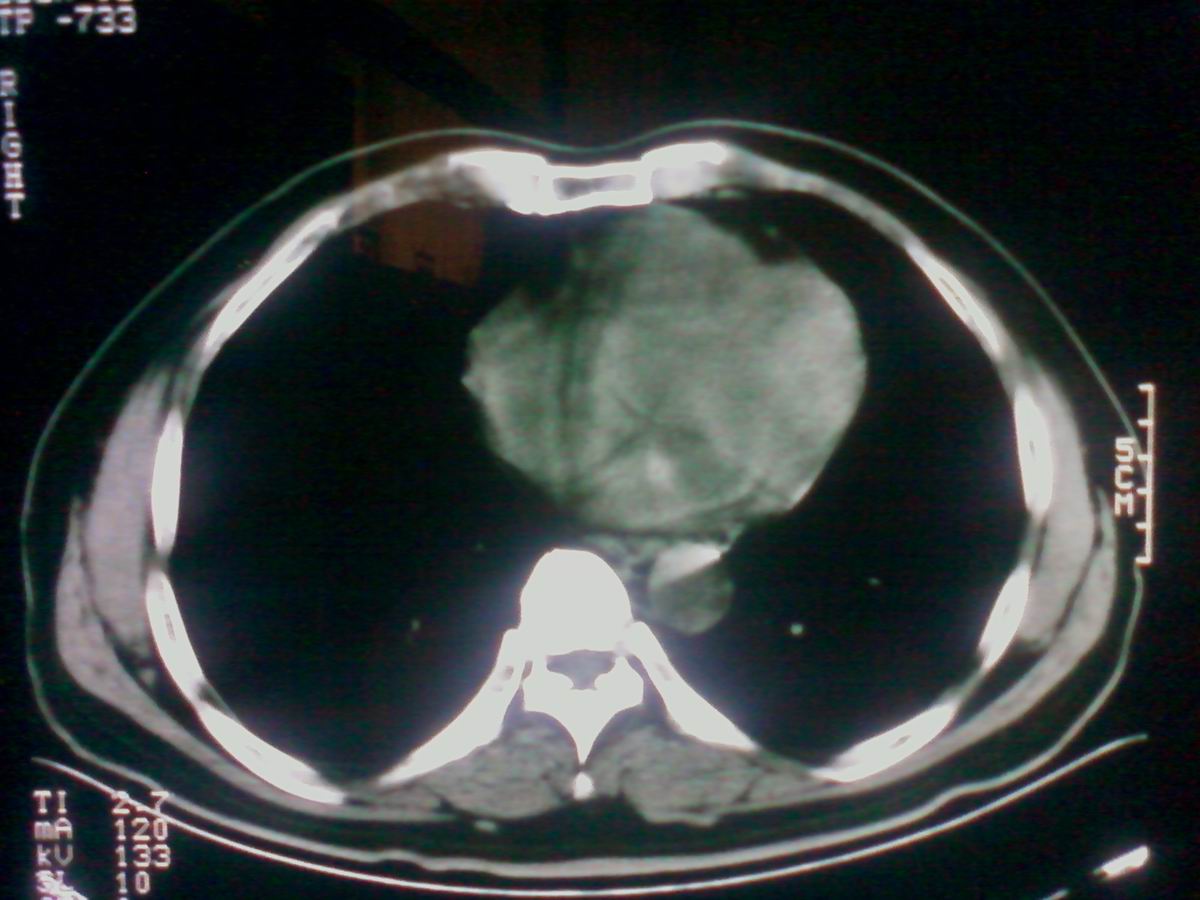

气管后部见半圆形软组织密度病灶,考虑占位,建议气管镜除外鳞癌。

气管上段的肿瘤多为良性乳头状瘤,气管下段的肿瘤多为鳞癌,气管中段的良恶性各占一半。本例位于气管下段,先按恶性处理。不过纤支镜是免不了的。

气管有占位鳞癌、腺样囊性癌、类癌、粘液表皮样癌。

进修时见过一例类似的并例,不过肿块位置较高,在胸锁关节以上的气管内,如果不是扫描得高,几乎忽略掉。后来支气管镜检为鳞癌。

考虑气管癌可能性大。